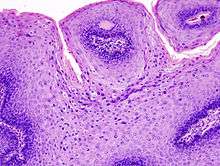

The diagnosis of genital warts is most often made visually, but may require confirmation by biopsy in some cases.[10] Smaller warts may occasionally be confused with molluscum contagiosum.[9] Genital warts, histopathologically, characteristically rise above the skin surface due to enlargement of the dermal papillae, have parakeratosis and the characteristic nuclear changes typical of HPV infections (nuclear enlargement with perinuclear clearing). DNA tests are available for diagnosis of high-risk HPV infections. Because genital warts are caused by low-risk HPV types, DNA tests cannot be used for diagnosis of genital warts or other low-risk HPV infections.[3]